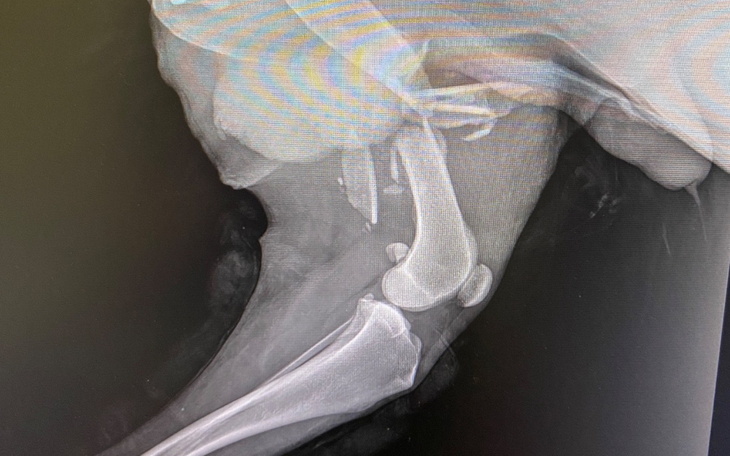

Sami zobaczcie jak pięknie chodzi 🩵 To wszystko dzięki ciężkiej pracy lekarzy z @aura_przychodnia_weterynaryjna, rehabilitacji w @rehavetbydgoszcz a przede wszystkim wspaniałym ludziom, u których przebywa Brunio 💖 Ogrom pracy, wyrzeczeń, nieprzespanych nocy, i poświęconego czasu całej rodziny wraz z wyżej wymienionymi placówkami postawiły Brunia na cztery łapy 🥹🥹🥹

Efekty tej ciężkiej pracy sami widzicie ❣️ Na ostatniej wizycie weterynaryjnej, lekarz powiedział, że jest pod ogromnym wrażeniem Bruna i jego stanu zdrowia 🥰

Bruno jest po operacji 🥹💙